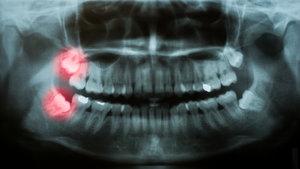

Adults have up to 32 teeth, of which four are wisdom teeth and these are the last to come through the gum. They are the one's right at the back of the mouth and usually appear between the ages of 17 and 25 although sometimes they can appear in later years.

If there is enough room in the mouth the wisdom teeth will come through (erupt) in a useful position and there will only be minor discomfort as they erupt. However, wisdom teeth can cause problems if there is not enough room in the mouth, as the wisdom tooth erupts at an angle and gets stuck against the tooth in front; the dentist will describe this as 'Impacted'.

The dentist will be able to assess whether there is sufficient room for the teeth to come through by taking an x- ray which will show the position of the root. Once the x-rays have been taken, the dentist will be able to tell how easy or difficult it will be to remove the tooth. The dentist will then determine whether the tooth should be taken out at the Dental Practice or by a Specialist Oral Surgeon.